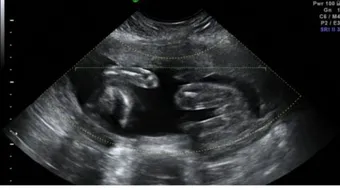

يمكن تحديد نوع الجنين في الثلث الأول من الحمل، وذلك ما بين الأسبوع التاسع من الحمل والأسبوع الثاني عشر، حيث يبدأ البرعم الجنسيّ للجنين بالتكوّن والظهور خارج جسمه مع بداية الأسبوع التاسع، ممّا يجعل من احتمال رؤيته والتعرف على نوعه ممكناً بمساعدة الأجهزة الفوق صوتيّة، إلا أنّ معظم الأطباء يفضلون الانتظار لما بعد الأسبوع الثاني عشر لتقديم النتيجة الأكيدة للوالدين حول نوع الجنين، حيث إنّ ظهور البرعم التناسلي ما بين الأسبوع التاسع والأسبوع الثاني عشر يكون في بداياته، مما يزيد من احتمال إعطاء نتيجة خاطئة، أما النتائج التي تقدم للوالدين بعد الأسبوع الثاني عشر فتكون أكيدة بنسبة 60%.

يعتمد الطبيب المختص في تمييز نوع الجنين على فحص البرعم التناسليّ للجنين، ففي حالة كونه ذكراً فإن برعمه التناسلي يكون متجهاً إلى الأعلى كما يتخذ وضعاً شبه أفقي، أما في حال كونها أنثى فإن برعمها التناسلي يكون متجهاً إلى الأسفل، كما يتخذ وضعاً أفقياً، ويفحص الطبيب اتجاه البرعم التناسلي عن طريق تحديد قياس الزاوية المرسومة بين مستقيمين، حيث يكون المستقيم الأول مماساً للجزء القطني العجزي للجنين، بينما يكون المستقيم الآخر مماساً للجزء البطني لبرعمه التناسلي، ففي حال كان قياس الزاوية أكثر من 30 درجة فإن الجنين ذكر، أما في حال عدم التقاء المستقيمين فعلى الأغلب أن الجنين أنثى، مع العلم أنّ نسبة الخطأ تتراوح ما بين 0.2% و3%.